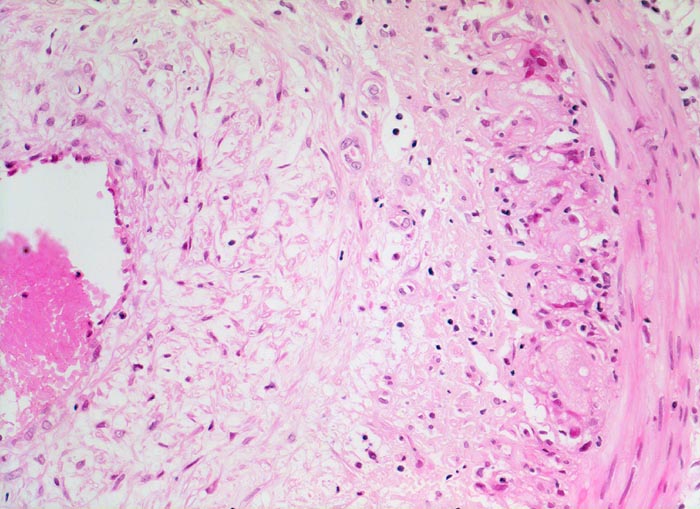

PathoPic – image database / PathoPic ID 4639 - Arteritis temporalis Horton (Riesenzellarteriitis)

Arteritis temporalis Horton (Riesenzellarteriitis)

Arteria temporalis

Ausgeprägte lockere Intimafibrose. Die Media ist deutlich dünner als die Intima. An der Grenze zwischen Media und Intima Reste einer stark fragmentierten Lamina elastica interna und ein gemischtes Entzündungsinfiltrat.

Histologie

200